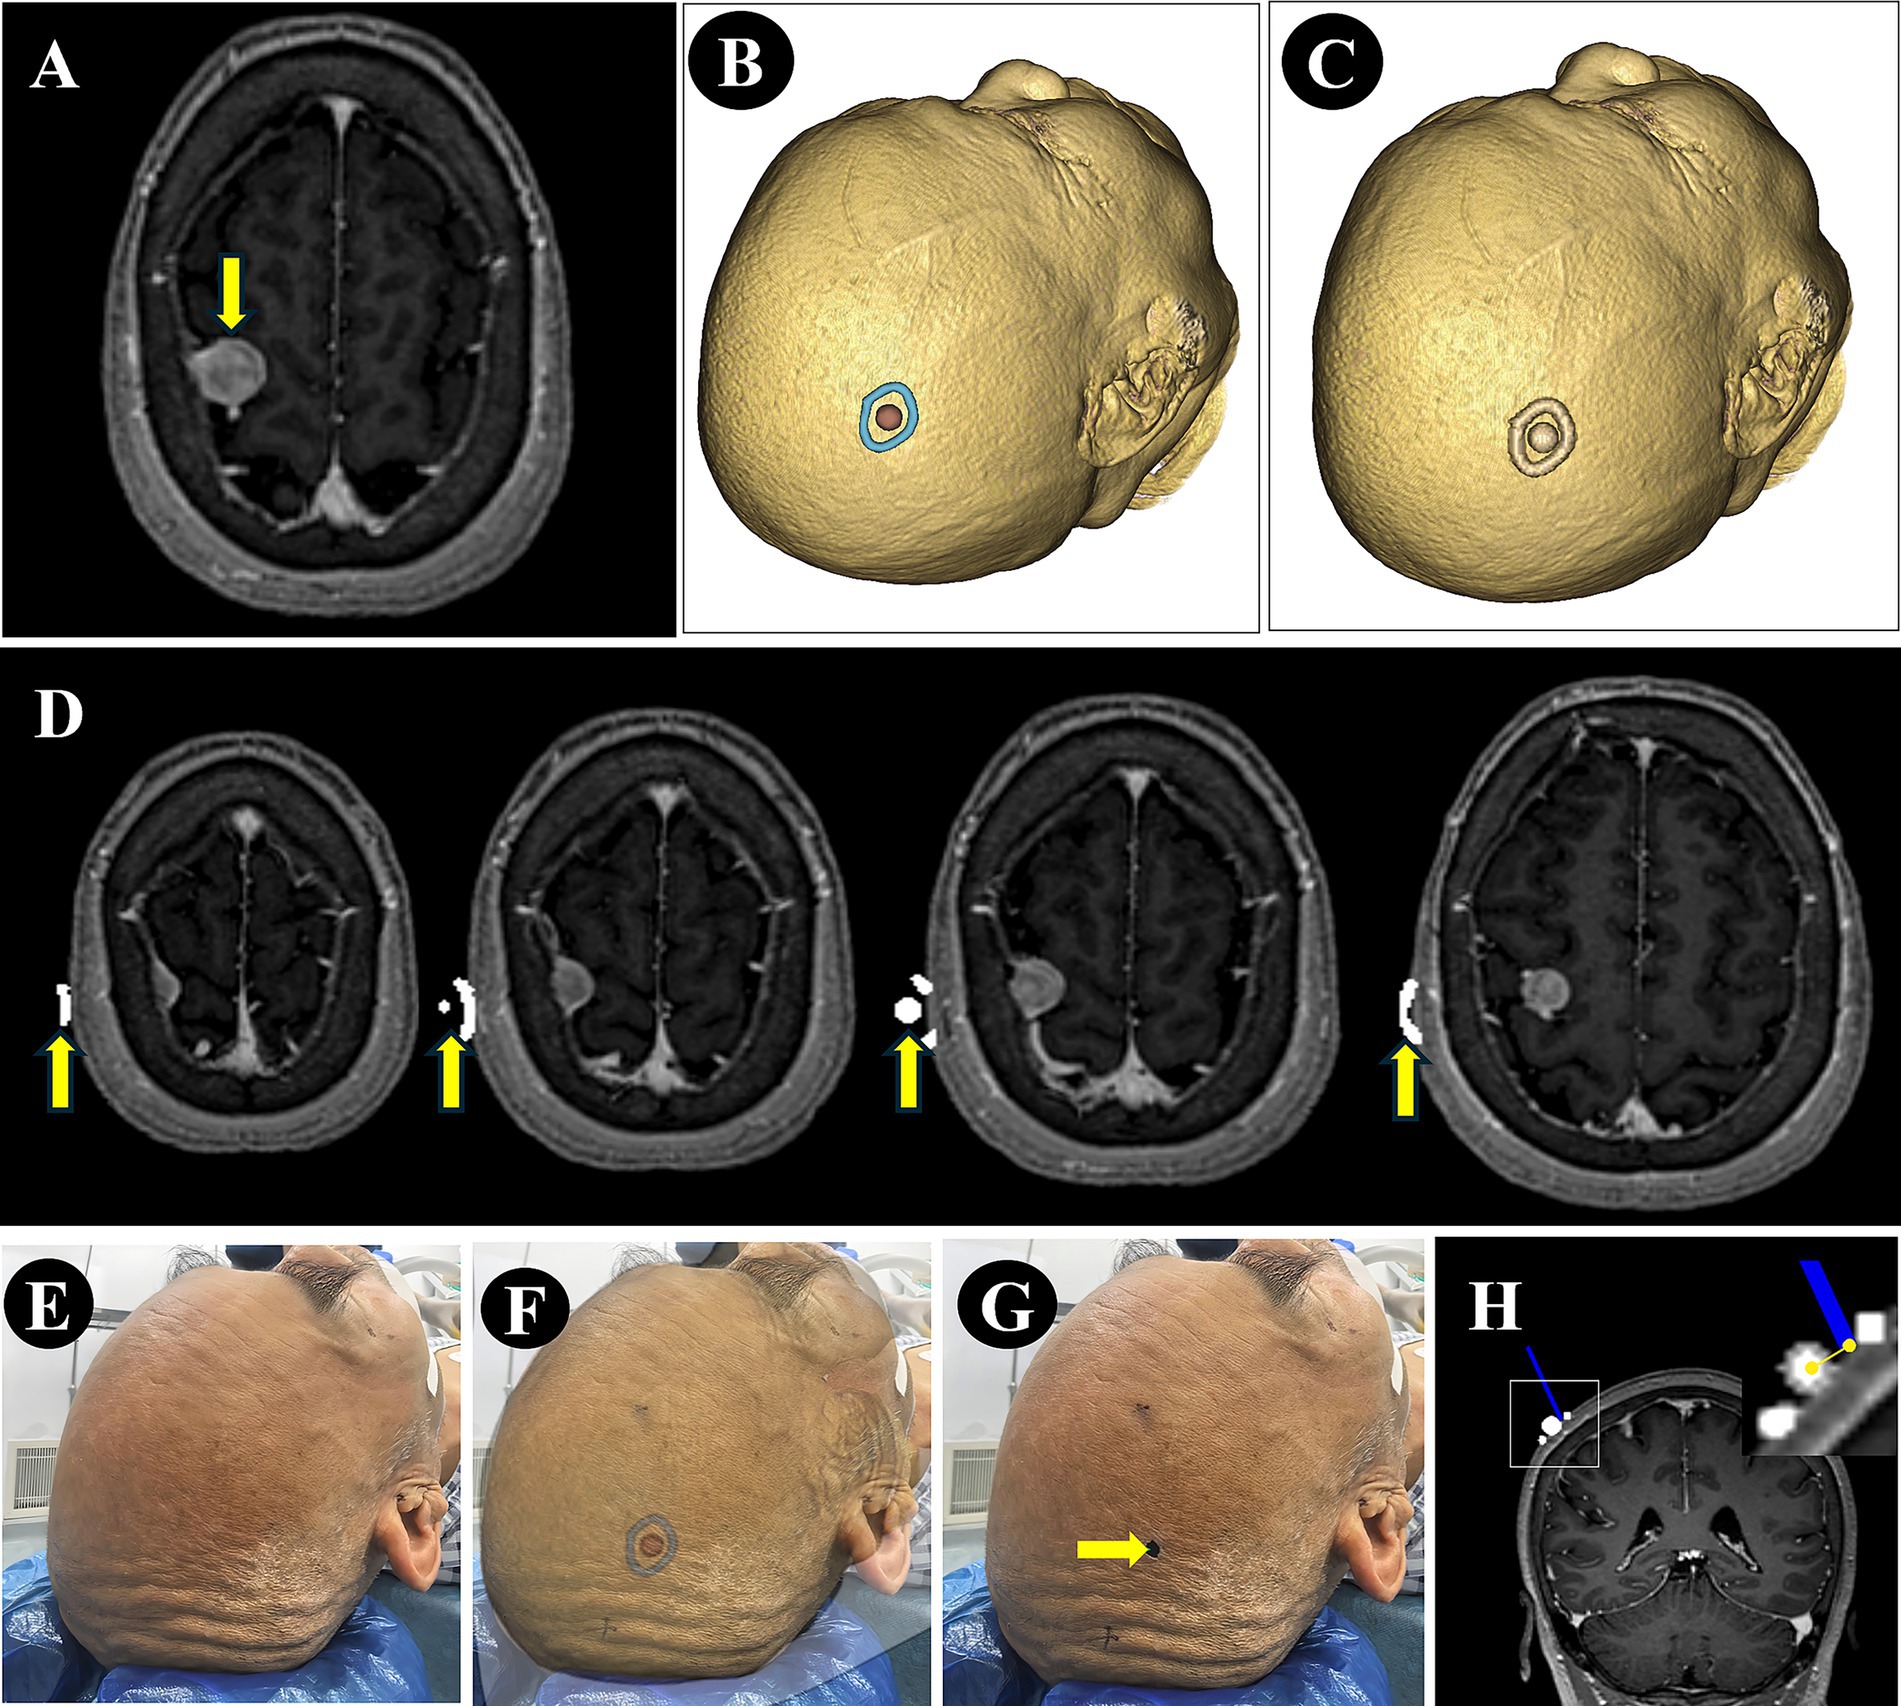

The NP-Guide functioned stably during use in this exploratory setting, with no startup failures or other system errors. Both physicians successfully performed preoperative localization at common surgical sites, including the temporal, frontal, and parietal regions (Figure 4).

Figure 4

Localization using NP-Guide. (A) Localization of a right temporal lesion. (B) Localization of a right parietal lesion. (C) Localization of a left temporal lesion. (D) Localization of a left frontal lesion.